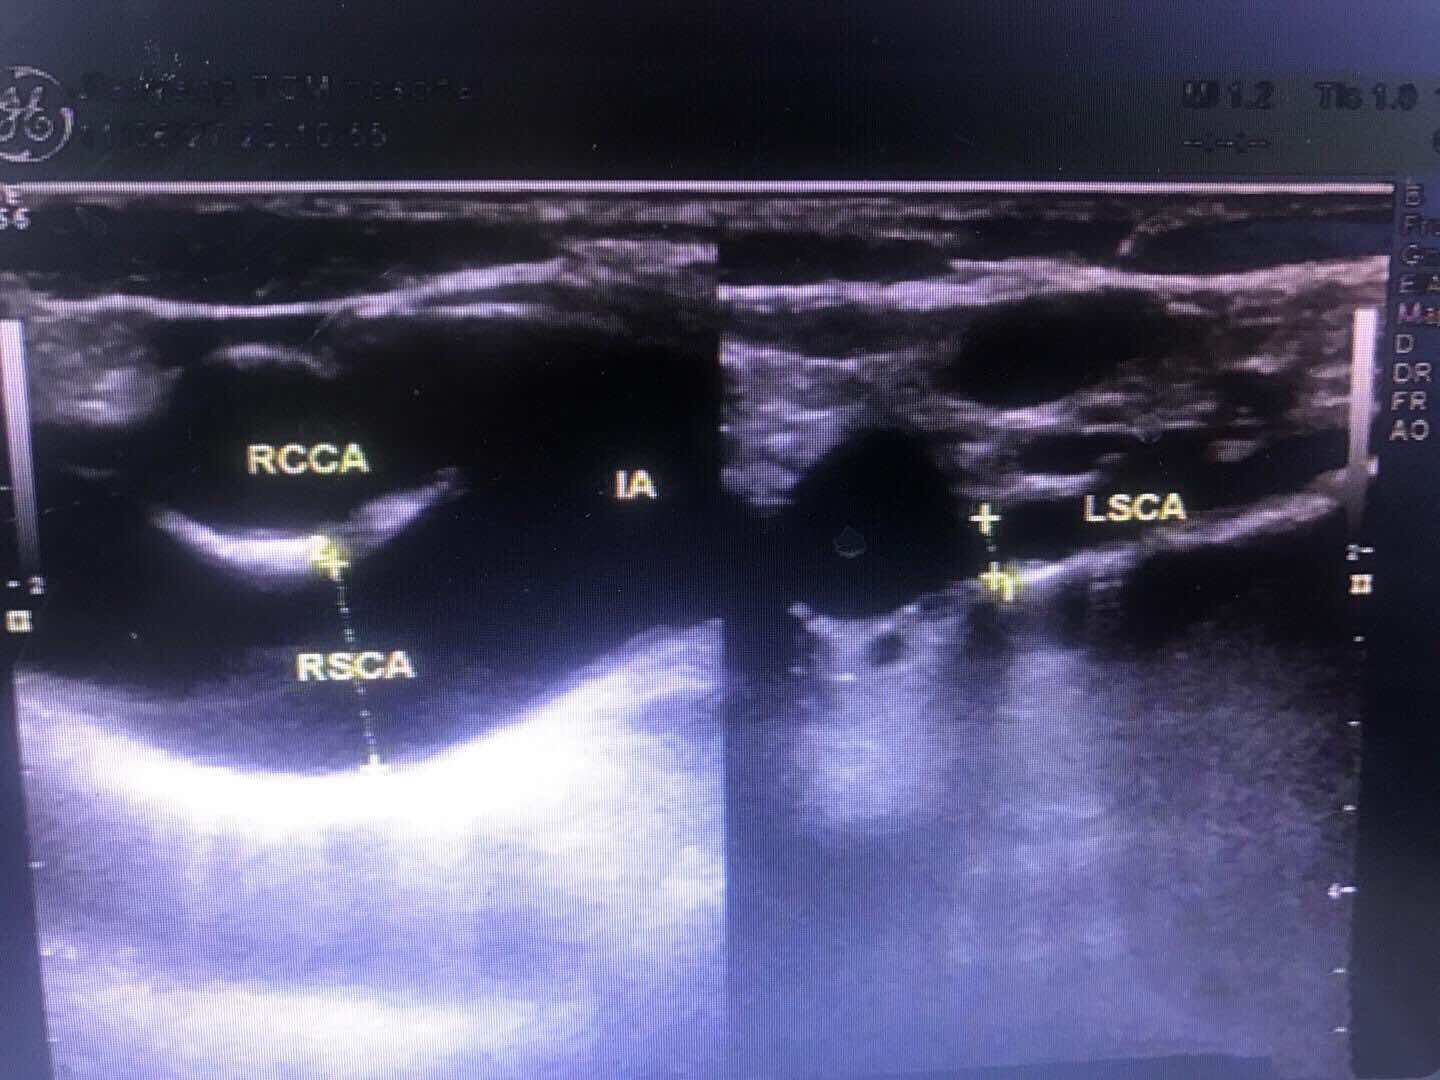

左侧桡动脉血流频谱,为低阻单相波形。左侧椎动脉和左侧颈总动脉血流,二者血流方向相反。 右侧和左侧锁骨下动脉起始部,左侧明显较右侧管径细。